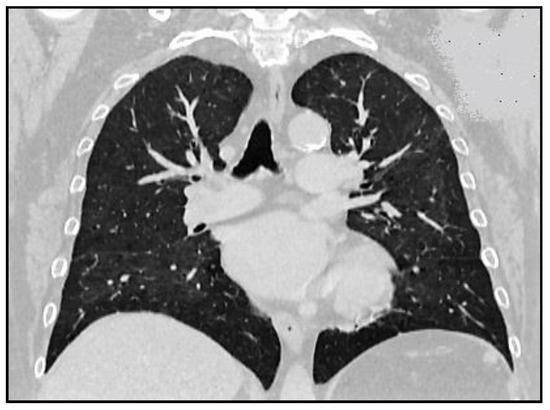

Imatinib-Induced Interstitial Pneumonitis—A Literature Review and Case Report

by Olga Hilda Orasan, Andreea Maria Stefan, Iulia Minciuna, Adela Sitar-Taut, George Ciulei, Simina Tarmure, Ioana Para, Flaviu Muresan, Ovidiu Fabian, Sorina Cezara Coste, Vasile Negrean, Angela Cozma and Laura Urian

Imatinib is generally well tolerated, with mild common side effects such as nausea and vomiting, diarrhea, muscle cramps, fatigue, skin rash and edema; however, pulmonary complications are uncommon. A 73-year-old woman undergoing one month treatment with Imatinib for chronic myeloid neoplasm associated with [...] Read more.

Imatinib is generally well tolerated, with mild common side effects such as nausea and vomiting, diarrhea, muscle cramps, fatigue, skin rash and edema; however, pulmonary complications are uncommon. A 73-year-old woman undergoing one month treatment with Imatinib for chronic myeloid neoplasm associated with eosinophilia was admitted for sudden alteration of her performance status, dyspnea at rest and productive cough. On clinical examination, the patient was hypoxic (oxygen saturation on room air was 87%), and auscultation of her lungs revealed diffuse bilateral fine crackles. Computed tomography showed bilateral pulmonary interstitial syndrome. Imatinib was discontinued and the patient received systemic corticosteroid therapy and oxygen therapy. After one month, the symptoms and radiological findings were resolved. When Imatinib therapy was resumed, respiratory symptoms reappeared, which is why treatment with Imatinib was interrupted. Imatinib-induced pneumonitis should take into consideration when patients develop respiratory symptoms or abnormal pulmonary radiological features. Full article

Show Figures

Figure 1